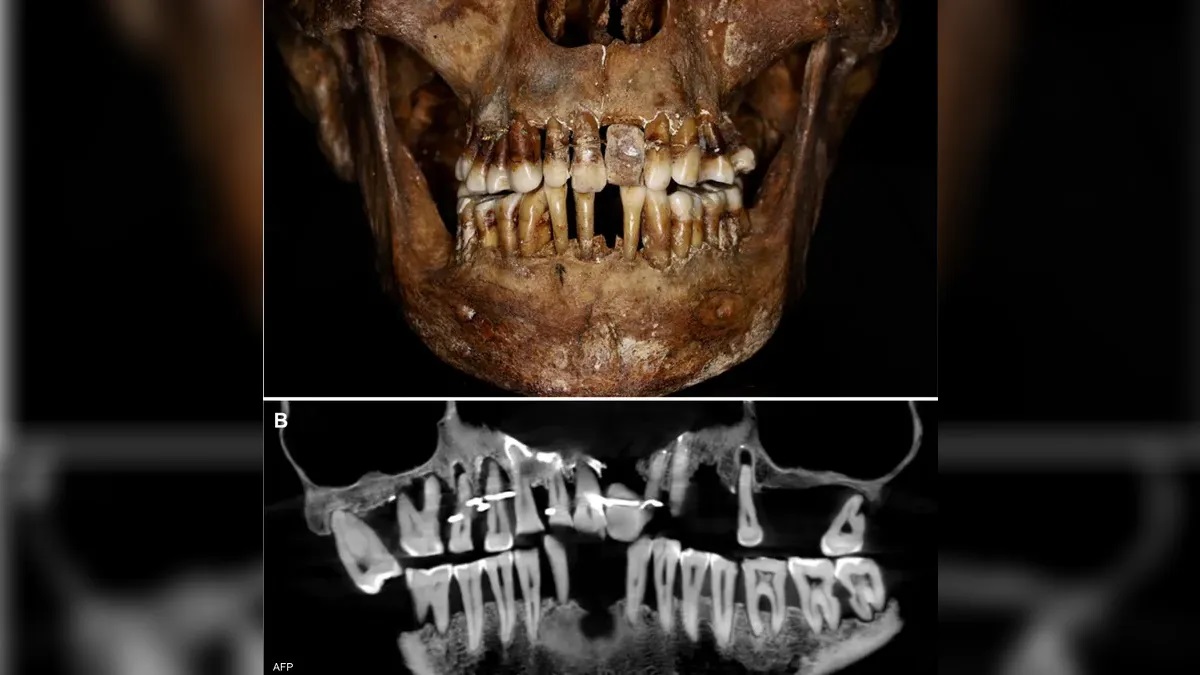

وتم العثور على جثة آن دليغري، التي توفيت عام 1619، أثناء التنقيب الأثري في شاتو دي لافال في شمال غرب فرنسا، محنطة في تابوت من الرصاص، هيكلها العظمي وأسنانها بحالة جيدة بشكل ملحوظ.

وحدد فريق من علماء الآثار وأطباء الأسنان أن دليغري كانت تعاني من مرض في اللثة أدى إلى تراجع أسنانها.

ووفق "سكاي نيوز عربية" أظهر مسح الأشعة السينية، أن السلك الذهبي قد استخدم لتماسك وشد العديد من أسنانها دليغري.

كما اكتشف الباحثون أن لديها أيضا سنا اصطناعية مصنوعة من عاج الفيل وليس من فرس النهر، الذي كان شائعا في ذلك الوقت.

وقال الباحثون إن الأسلاك الذهبية كانت تحتاج إلى شد متكرر على مر السنين، الأمر الذي زاد من زعزعة استقرار الأسنان المجاورة.